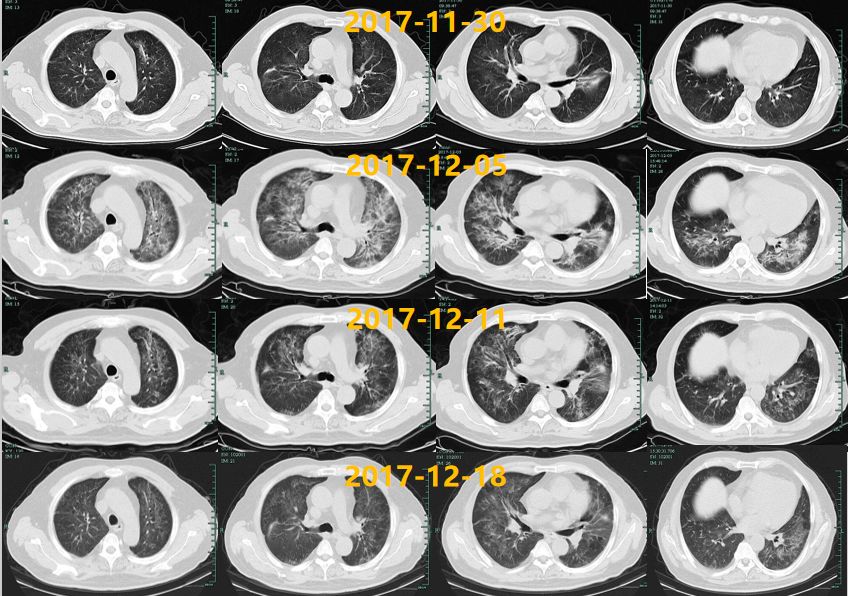

【图2】12月5日肺部CT复查提示两肺弥漫渗出影伴肺间隔增厚,较11.30明显进展

【图3】诊治期间肺部CT变化